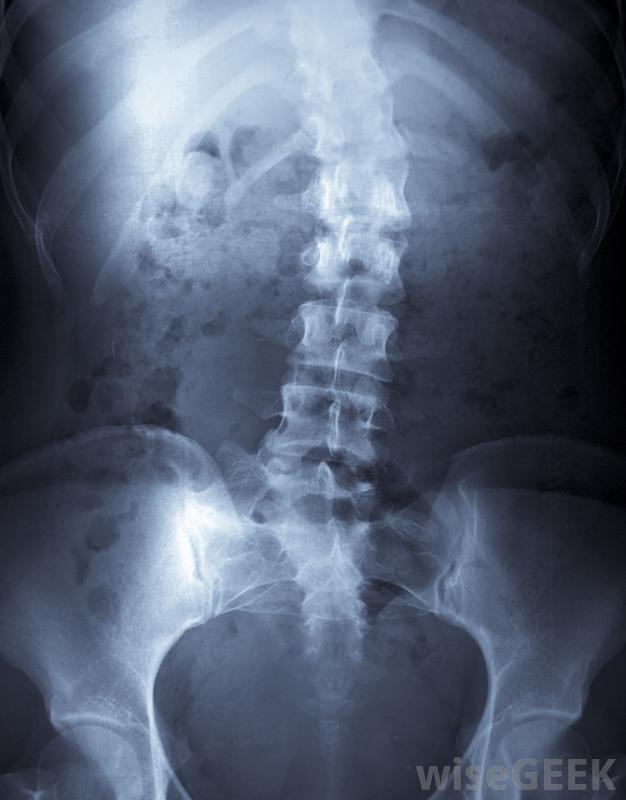

最常見的脊柱融合并發癥是什么(Most Common Spinal Fusion Complications)?

手術后患者可能會遇到許多脊柱融合并發癥,包括神經損傷、慢性背痛和感染。脊柱融合是一項復雜的醫療過程,需要將椎骨融合在一起。愈合過程可能需要長達一年的時間,并發癥的風險比其他醫療程序高。盡管醫療進步和更好的病人護理已經降低了主要并發癥的可能性,脊柱側凸是脊柱異常彎曲的一種治療方法脊柱融合術是兩個或兩個以上的椎骨融合在一起的一種醫療程序。這可能有很多原因,但最常見的是脊柱側凸的矯正,外科醫生將脊柱伸直,將尸體骨插入椎骨之間,尸體骨起到橋梁的作用,使脊椎融合在一起,一旦愈合,脊柱將保持挺直,融合的骨頭阻止了脊柱側彎的進一步發展脊柱融合是兩個或多個椎骨融合在一起的醫療過程脊柱融合并發癥包括手術引起的不同程度的神經損傷。由于脊柱融合涉及整個背部,手術可以切斷許多周圍神經在康復過程中,隨著神經的愈合,患者可能會出現各種癥狀;失去感覺或對觸覺過敏的情況并不少見。許多月或數年的時間可能會讓患者體驗到更多正常的感覺。即使如此,觸覺的減弱可能會在患者的余生中持續存在接受脊柱融合術的患者可能會出現神經損傷、慢性背痛或感染,具體取決于位置和程度在脊柱融合術中,慢性背痛可能成為患者脊柱融合術并發癥的一部分。例如,矯正脊柱側凸的脊柱融合術涉及到大量肌肉組織的切割。即使在肌肉完全愈合后,患者也可能比手術前出現更多的背痛脊柱融合術的另一個并發癥是術后感染。抗抗生素的細菌如MRSA對所有住院病人都有風險。那些免疫系統受到抑制或從任何類型的手術中恢復過來的患者風險更大是非常危險的,并且會使脊柱融合的恢復變得非常復雜。歷史上,最常見的脊柱融合并發癥包括不正確或失敗的融合。從20世紀初開始,術后病人將被固定在石膏內長達一年20世紀50年代,Harrington棒的引入降低了并發癥的總體幾率,盡管患者仍需花費數月時間進行一系列的石膏和支架治療。Harrington棒技術的進步已經消除了對術后支架的需求。今天,患者的融合不太可能失敗或設置不正確。脊柱各部分。